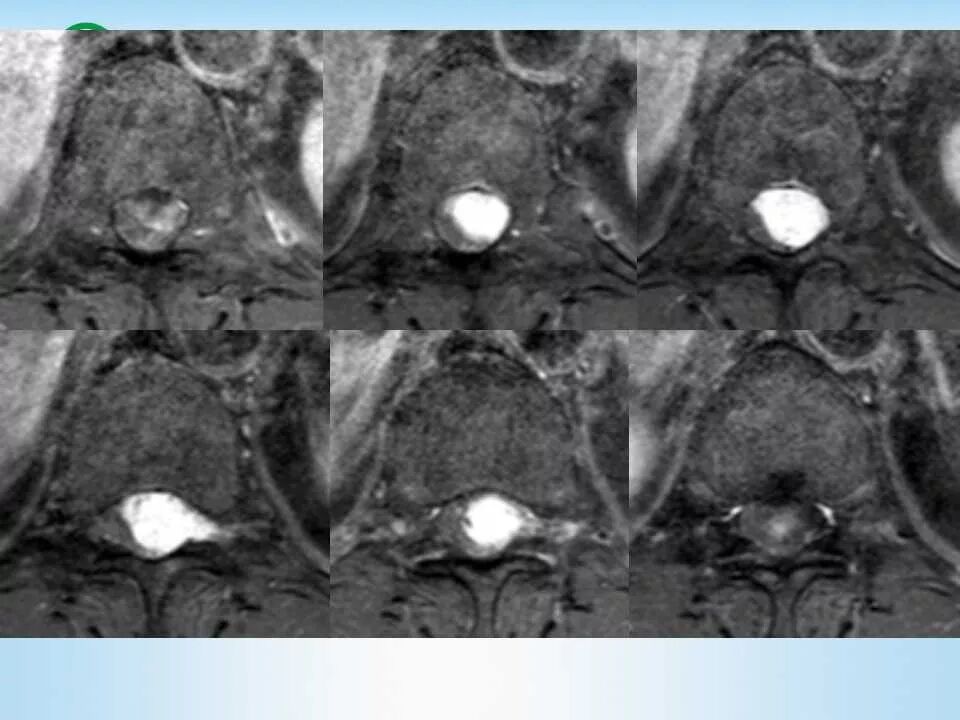

北方影像联盟 一周病例精选之“椎管占位”